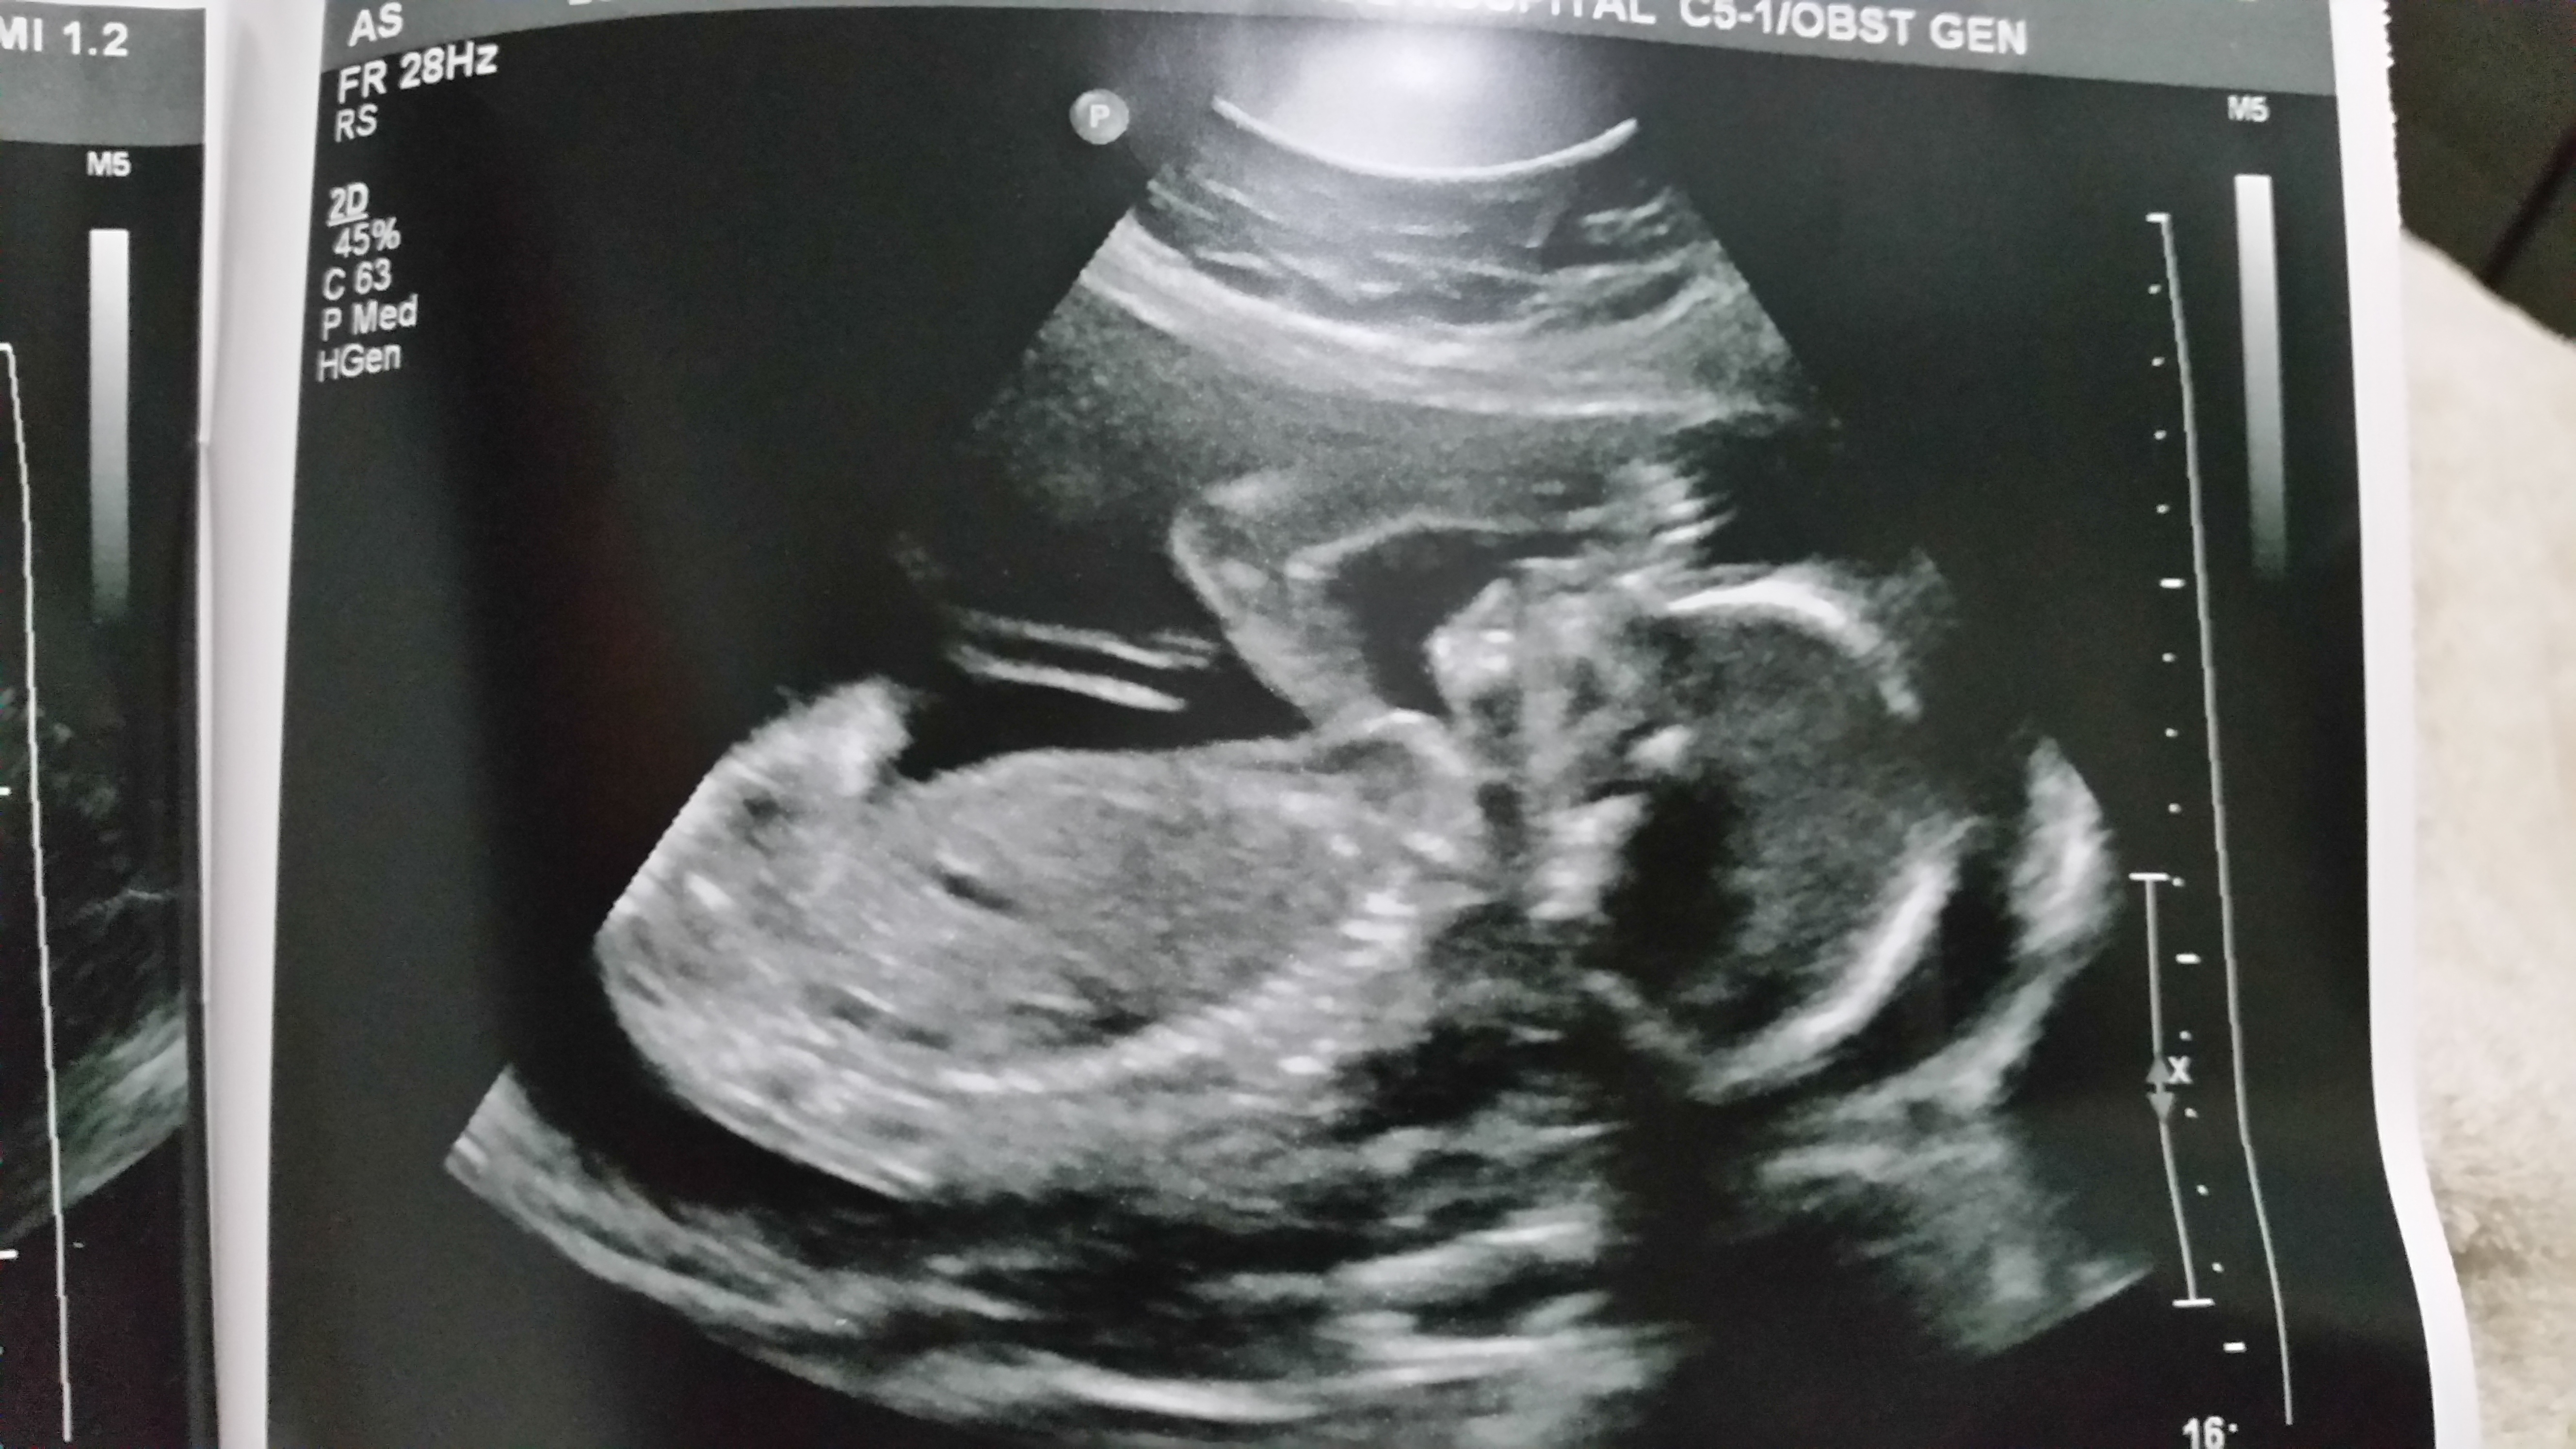

Update i just had my 25 week a 1 day scan please scroll down for latest pics.